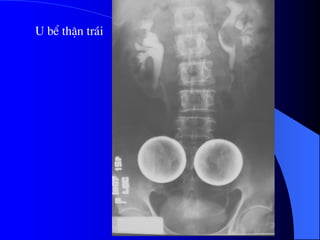

U bÓ thËn tr¸i

4.2. U bãøtháûn, niãûu quaín vaì baìng quang * Laì loaûi u biãøu mä âæåìng dáùn niãûu aïc tênh, chiãúm 6-10% caïc u tháûn aïc tênh. Caïc yãúu täú nguy cå chênh laì soíi tiãút niãûu, nhiãùm truìng, nghiãûn thuäúc laï, duìng quaï nhiãöu thuäúc phenacetin. Hay gàûp > 50tuäøi, nam = 2næî. * U laình tênh: polyp, hay gàûp âäü tuäøi 20-40. * U aïc tênh: chuí yãúu Carcinome tãú baìo chuyãøn tiãúp (85%), ngoaìi ra Carcinome tãú baìo vaíy (15%). Di càn ung thæ âãún âæåìng dáùn niãûu hiãúm gàûp. * U âæåìng dáùn niãûu hay gàûp theo thæï tæû åí baìng quang, bãø tháûn, niãûu quaín.

- NÂTM + Âäúivåïi thãø thám nhiãùm coï hçnh aính heûp, båì khäng âãöu, thæåìng gáy æï næåïc. + Âäúi våïi thãø suìi, coï hçnh khuyãút saïng trong âæåìng dáùn niãûu, båì coï thãø khäng âãöu, coï thãø gáy æï næåïc âæåìng dáùn niãûu phêa trãn. Cáön phán biãût våïi cuûc maïu âäng vaì soíi KCQ. ٠Soíi vaì maïu cuûc di chuyãøn vë trê, coï viãön caín quang bao quanh. ٠Maïu cuûc thay âäùi hçnh daûng theo thåìi gian. ٠U âæåìng dáùn niãûu (bãø tháûn, niãûu quaín, baìng quang) coï hçnh aính chán baïm vaìo thaình, nåi khäng coï viãön TCQ bao quanh u.